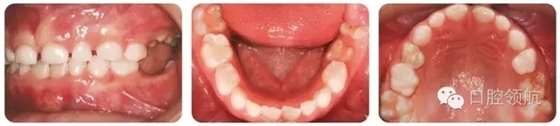

圖2.10的上頜牙列特征有哪些?

圖2.10

早期恒牙列患者,UL3腭側(cè)錯(cuò)位萌出。左上頜乳尖牙滯留。UR6輕度發(fā)育不全。

治療方法

拔除滯留且阻擋恒牙的乳尖牙。

圖2.11中有哪些明顯的牙列異常?

圖2.11

ULE和LLE低位咬合。